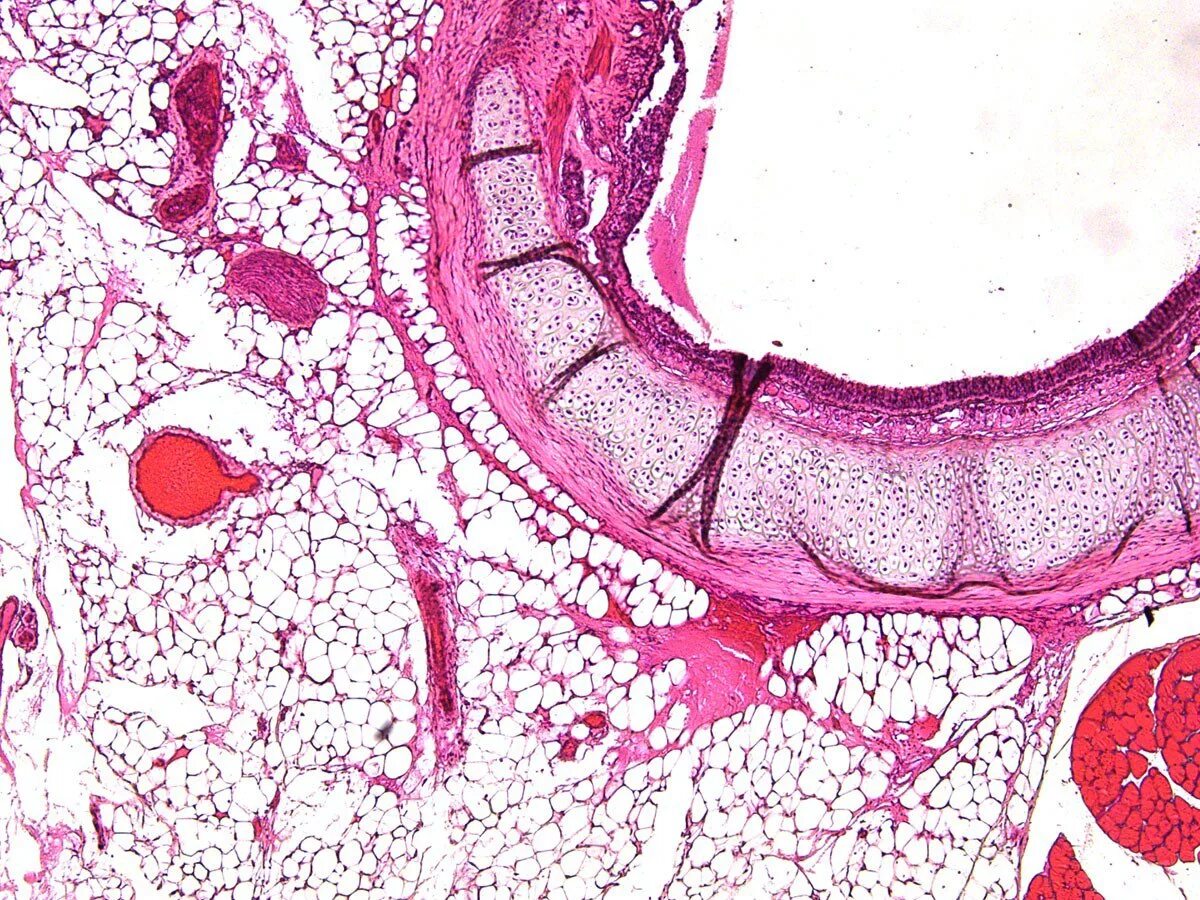

Гистологическое исследование слизистой